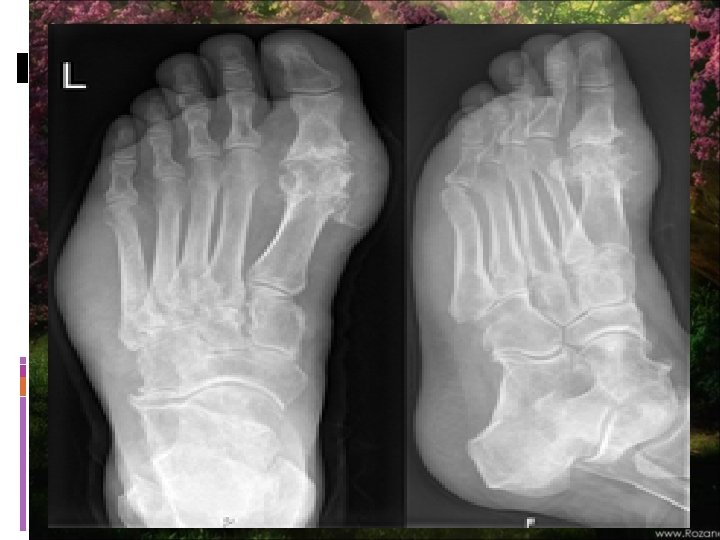

Chronic Gout-Radiographic Features

Radiographic Features Early in the disease radiographic studies may only confirm clinically evident swelling. Cystic changes, well-defined erosions with sclerotic margins (often with overhanging bony edges), and soft tissue masses are characteristic features of advanced chronic tophaceous gout. Ultrasound, CT and MRI are being studied and are likely to become more sensitive for early changes